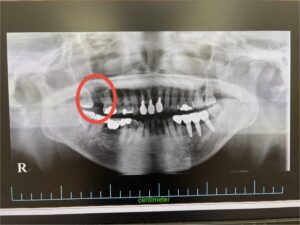

<インプラント実例掲載>以前のインプラント治療経過ご報告

こんにちは!インプラント認定医のホウショです。 2020.05.13に掲載させて頂いたインプラント治療の経過を今回はご紹介致します。 2020.05.13の時点ではまだ患者さんにとっての左奥歯のインプラントの被せ物が入っ […]

2020.12.26 インプラント実例